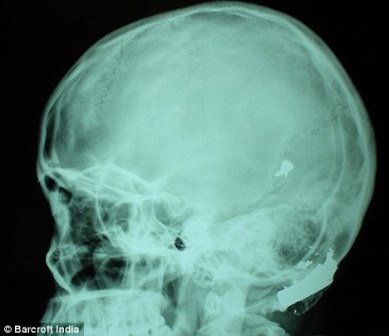

X光片顯示子彈嵌在了赫娜的腦子里

其中一顆子彈擊中她的左中耳,穿透了她的耳骨,然后擊中頭骨,嵌在了腦子里。另外兩顆子彈分別擊中她的右臂和心臟。印度Lok Nayak醫院的醫生稱,赫娜能夠康復完全是奇跡,她也足夠幸運。她的主治醫生稱:“當我們看到她的情況時,被嚇了一跳,幸運的是她活了下來。”

這顆子彈沒有損壞大腦中控制身體機能的部分。盡管赫娜的手術很成功,但醫生表示,她還有出現感染和并發癥的可能。子彈毀掉了她的中耳,可能導致她耳聾。(楊柳)